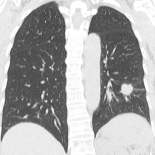

胸部CT |

画像検査の見落としがないよう各科専門の医師による確認後、読影専門医による画像確認のダブルチェックを実施しております。

頭部MRIは、脳神経外科の専門医がチェックします。